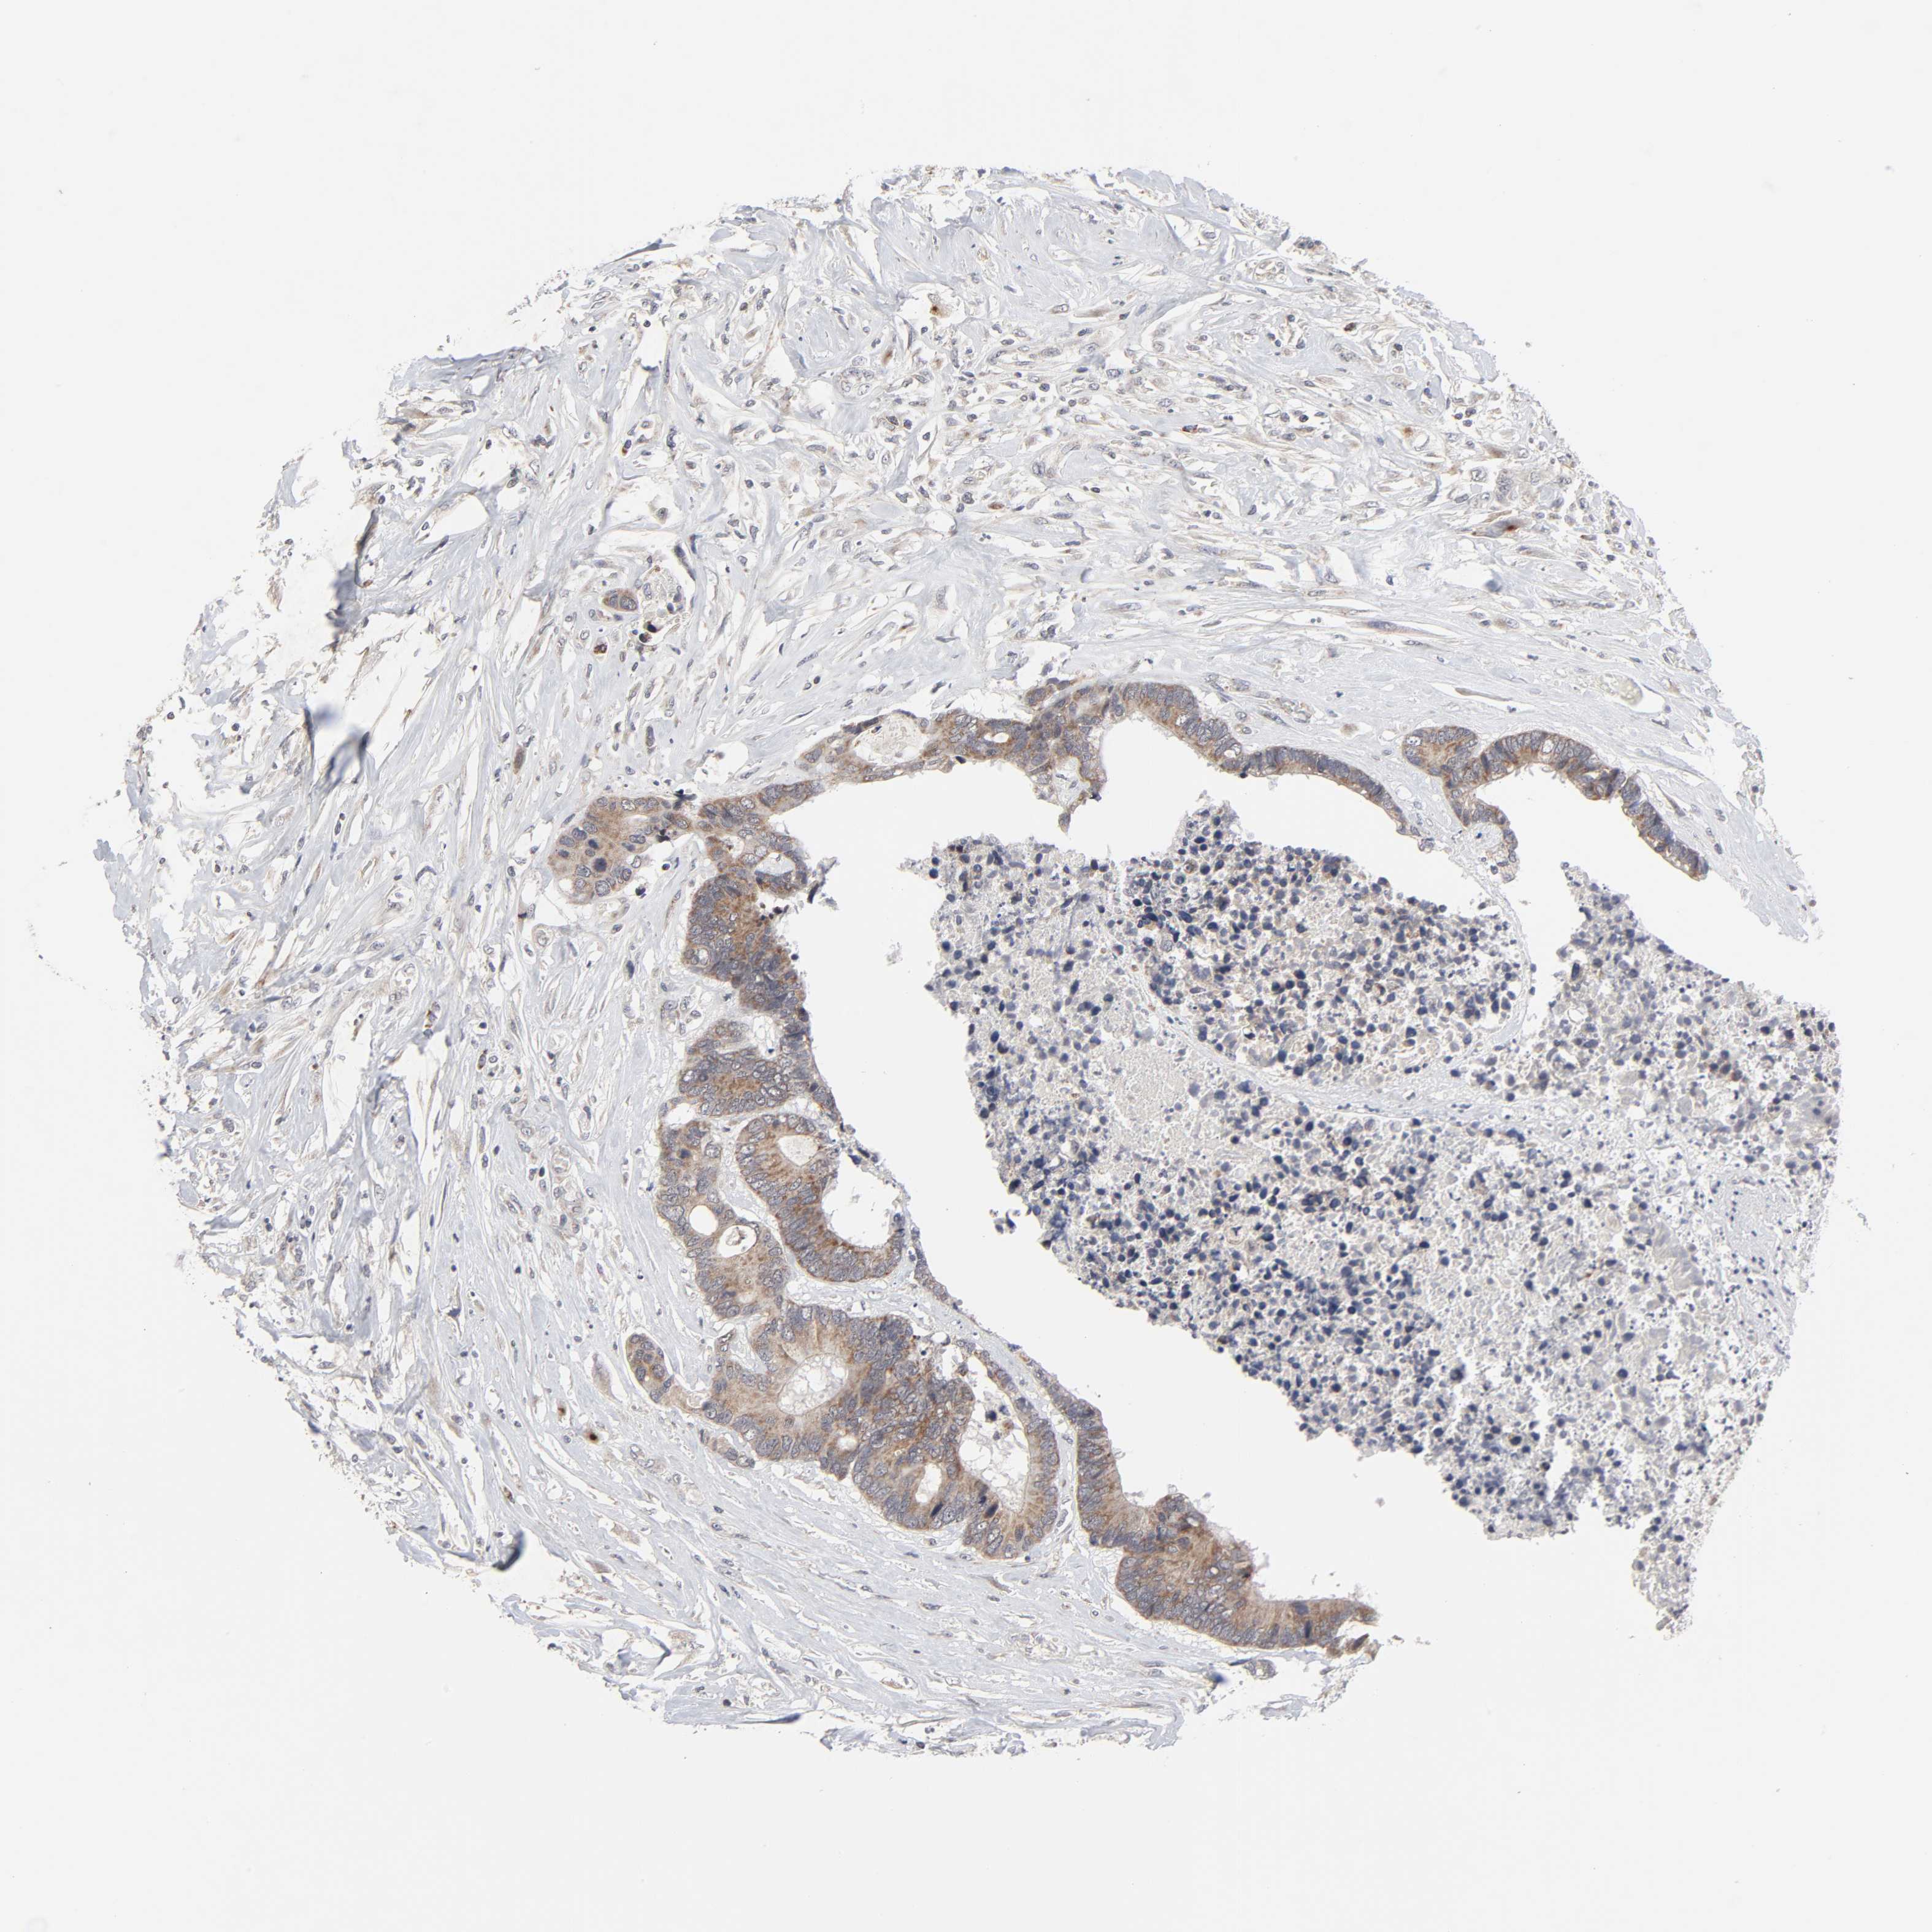

CANCER COLORECTAL CANCER Show tissue menu

Colorectal cancer

Human cancer

Colon adenocarcinoma